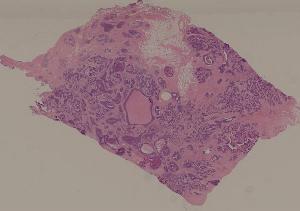

80. Invasive ductal cancer of the breast